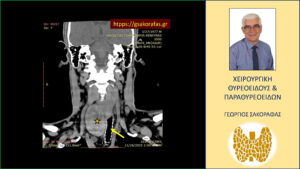

Καταδυόμενη βρογχοκήλη με πιεστικά φαινόμενα από την τραχεία – με αφορμή ασθενή μας (εικόνες). Ο διογκωμένος καταδυόμενος δεξιός λοβός του θυρεοειδούς (κίτρινος αστερίσκος) απωθεί προς τα αριστερά την τραχεία (κίτρινο βέλος). Εικόνα σε κατά μέτωπον διατομή.

Για την αξιολόγηση του βαθμού κατάδυσης του δεξιού λοβού στο μεσοθωράκιο ο ασθενής υποβλήθηκε σε αξονική τομογραφία, στην οποία απεικονίζεται σημαντικού βαθμού αύξηση των διαστάσεων του θυρεοειδούς και κυρίως του δεξιού λοβού (δεξιός λοβός 74 x 57 x 50 mm, αριστερός λοβός 63 x 33 x 21 mm). Ο δεξιός λοβός καταδύεται στο μεσοθωράκιο. Απωθεί την τραχεία προς τα αριστερά.

Και στην αξονική τομογραφία δεν παρατηρήθηκαν ύποπτοι ή παθολογικοί τραχηλικοί λεμφαδένες. Εικόνα συμβατή με καταδυόμενη ευμεγέθη βρογχοκήλη.